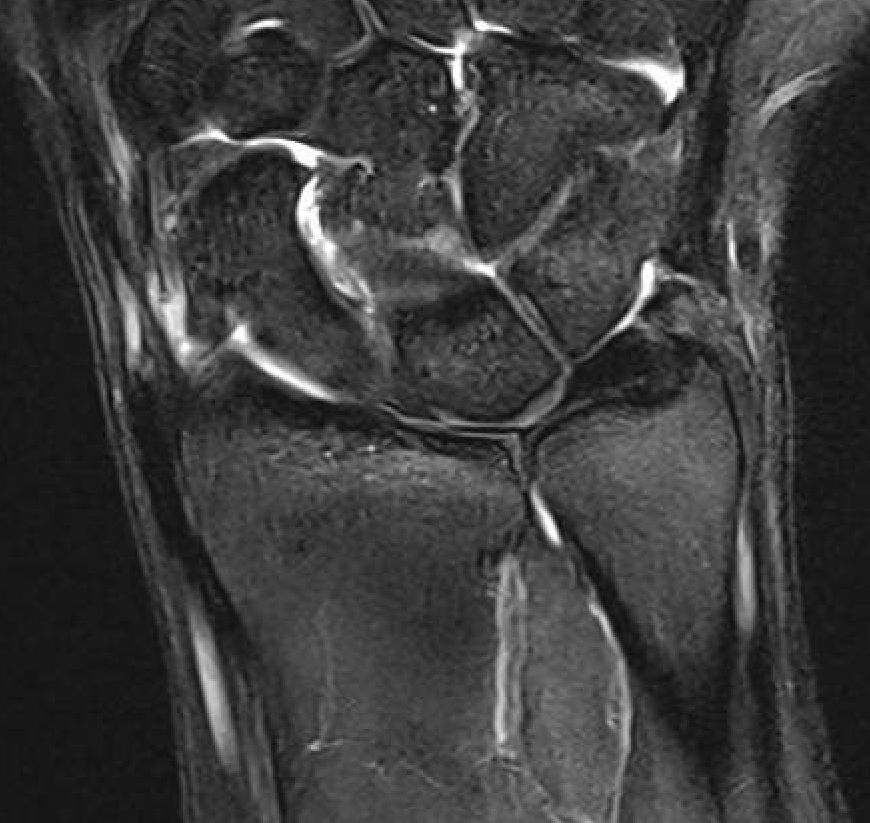

MRI

Normal

TFCC tears

Ulna sided tear

Radial sided TFCC tear

Central TFCC tear

Ulno-carpal abutment

Ulnocarpal abutment and lunate chondromalacia

Ulna positive with ulnocarpal osteoarthritis

Central TFCC tear with ulna positive variance an ulnocarpal abutment on MRI